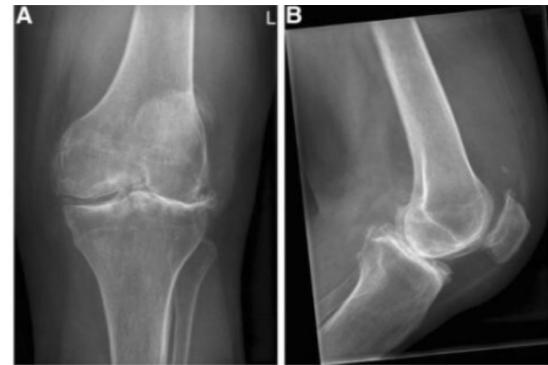

A 60-year-old overweight lady presented to clinic with chronic pain in both knees. A standing AP x-ray of both knees is shown.

Q1: Mention TWO findings on this X-ray

- Narrowing of the joint space

- Osteophytes

Q2: What is the diagnosis?

- Bilateral knee osteoarthritis